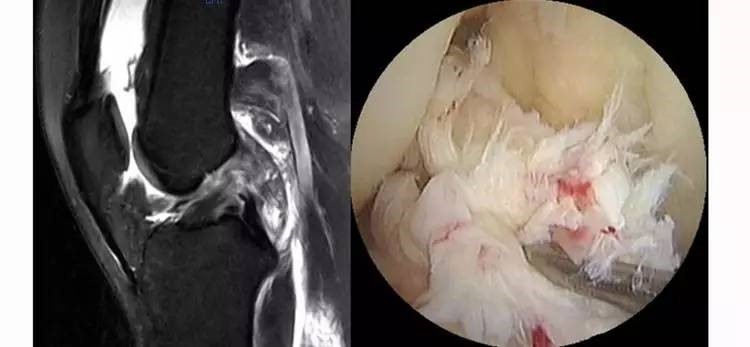

前交叉韧带(ACL)损伤的MRI诊断

前交叉韧带(ACL)损伤是青壮年膝关节最常见的运动损伤,损伤后膝关节肿胀、疼痛,活动受限。虽然肿胀消退后绝大多数人行走都正常,但膝关节常有不稳感,不能进行急停、急转等动作。受伤后,核磁共振(MRI)是必不可少的检查手段,尽管我国MRI已经基本普及,但诊断的准确性还不够高,因此,如何提高MRI的阅片水平是相关学科的医生特别是刚刚进入运动医学领域的医生迫切需要解决的问题。文中,广西中医药大学第一附属医院米琨教授就前交叉韧带(ACL)损伤的MRI诊断进行了详细讲授。

ACL损伤的直接征象:指ACL本身的形态和信号异常。一旦有了明确的直接征象就可以确定ACL损伤。

1.不连续:有韧带的低信号,但中断不连续。一般见于新鲜损伤。

2.方向异常(ACL 下垂征):有较完整的韧带低信号,但方向异常,呈下垂状。一般见于股骨附着部的陈旧损伤,损伤的ACL下垂并粘附在PCL上。

3.ACL 消失:髁间窝空虚,无韧带信号。见于较久的损伤,损伤的ACL撕裂较重呈马尾状,无滑膜包裹,逐渐被关节内的酶腐蚀而消失。

5.假瘤:韧带损伤后断端较整齐,残端组织增生并被滑膜包裹呈'瘤状',如果突出于前方为'独眼征',多见于韧带股骨附着部撕裂及部分撕裂。

6.扭曲和空虚:髁间窝内似隐隐约约有低信号,边缘明显,中央空虚;或者中央有低信号,但扭曲如麻花状。多为陈旧损伤,仅存ACL的滑膜,里面可有少量的韧带纤维,粘附在后方,随着膝关节的长时间屈伸逐渐呈扭曲状。